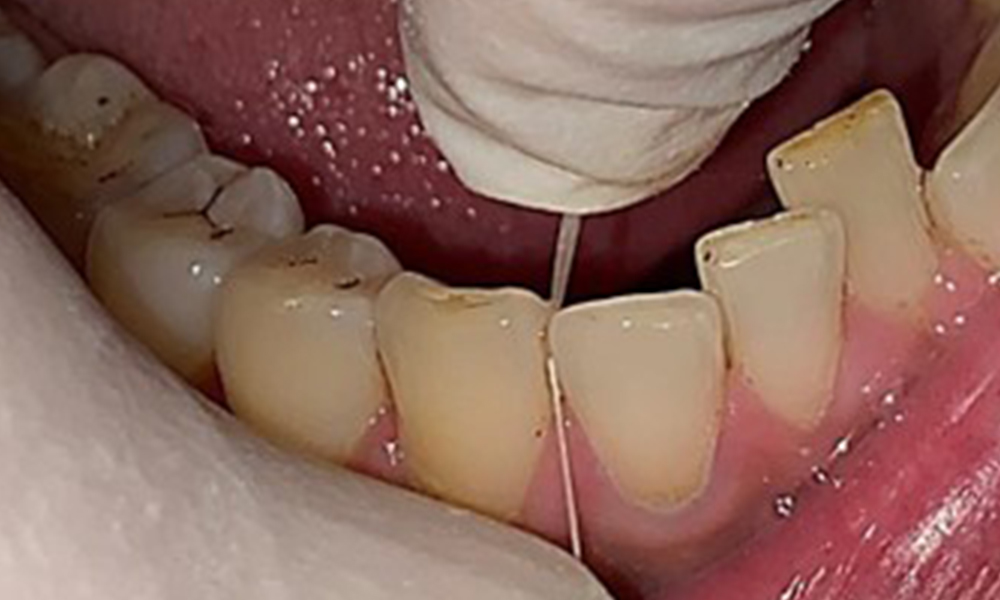

Instruktion & Motivation sind wichtige Bestandteile in der Sitzung. Gutes

häusliches Mundhygieneverhalten und – verständnis sind dem Patienten wichtig. Es zeigen sich insbesondere an den ZahnhalsbereichenPlaqueakkumulationen (Abb. 8).

Plaqueakkumulationen im Zervikalbereich

Abb. 8: Die Pfeile markieren Plaqueakkumulationen im Zervikalbereich, © Dr. R. Krapf

Diese sind mit dem Patienten zu besprechen und Verbesserungen in der Zahnputztechnik zu üben. Gerade aufgrund der Erosionen und Attritionen ist ein weicher Zahnbürstenaufsatz für die häusliche Mundhygiene anzuraten.